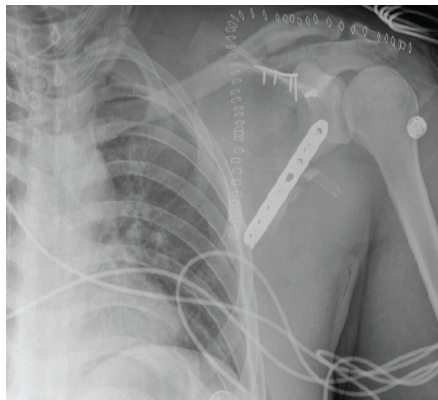

Postoperatively, the patient was immobilized in a sling for 6 weeks. Post-operative radiographs and CT imaging confirmed anatomic reduction and appropriate hardware placement (Fig. 4 and 5). Pain was managed with an epidural and ketamine infusion, and neurorehabilitation planning was initiated. The patient tolerated the procedure well and was discharged with a comprehensive recovery plan.

Figure 4: Post-operative anteroposterior radiograph of the left shoulder demonstrating internal fixation of the comminuted left scapular fracture.